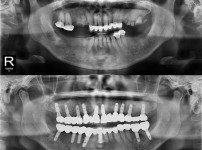

全口种植牙